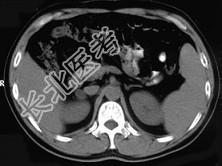

- 单项选择题女,23岁, 满月脸、向心性肥胖,CT扫描如图所示, 应诊断为 ( )

A、右侧肾上腺增生

B、右侧肾上腺腺瘤

C、右侧肾上腺腺癌

D、右侧肾上腺嗜铬细胞瘤

E、右侧肾上腺转移瘤